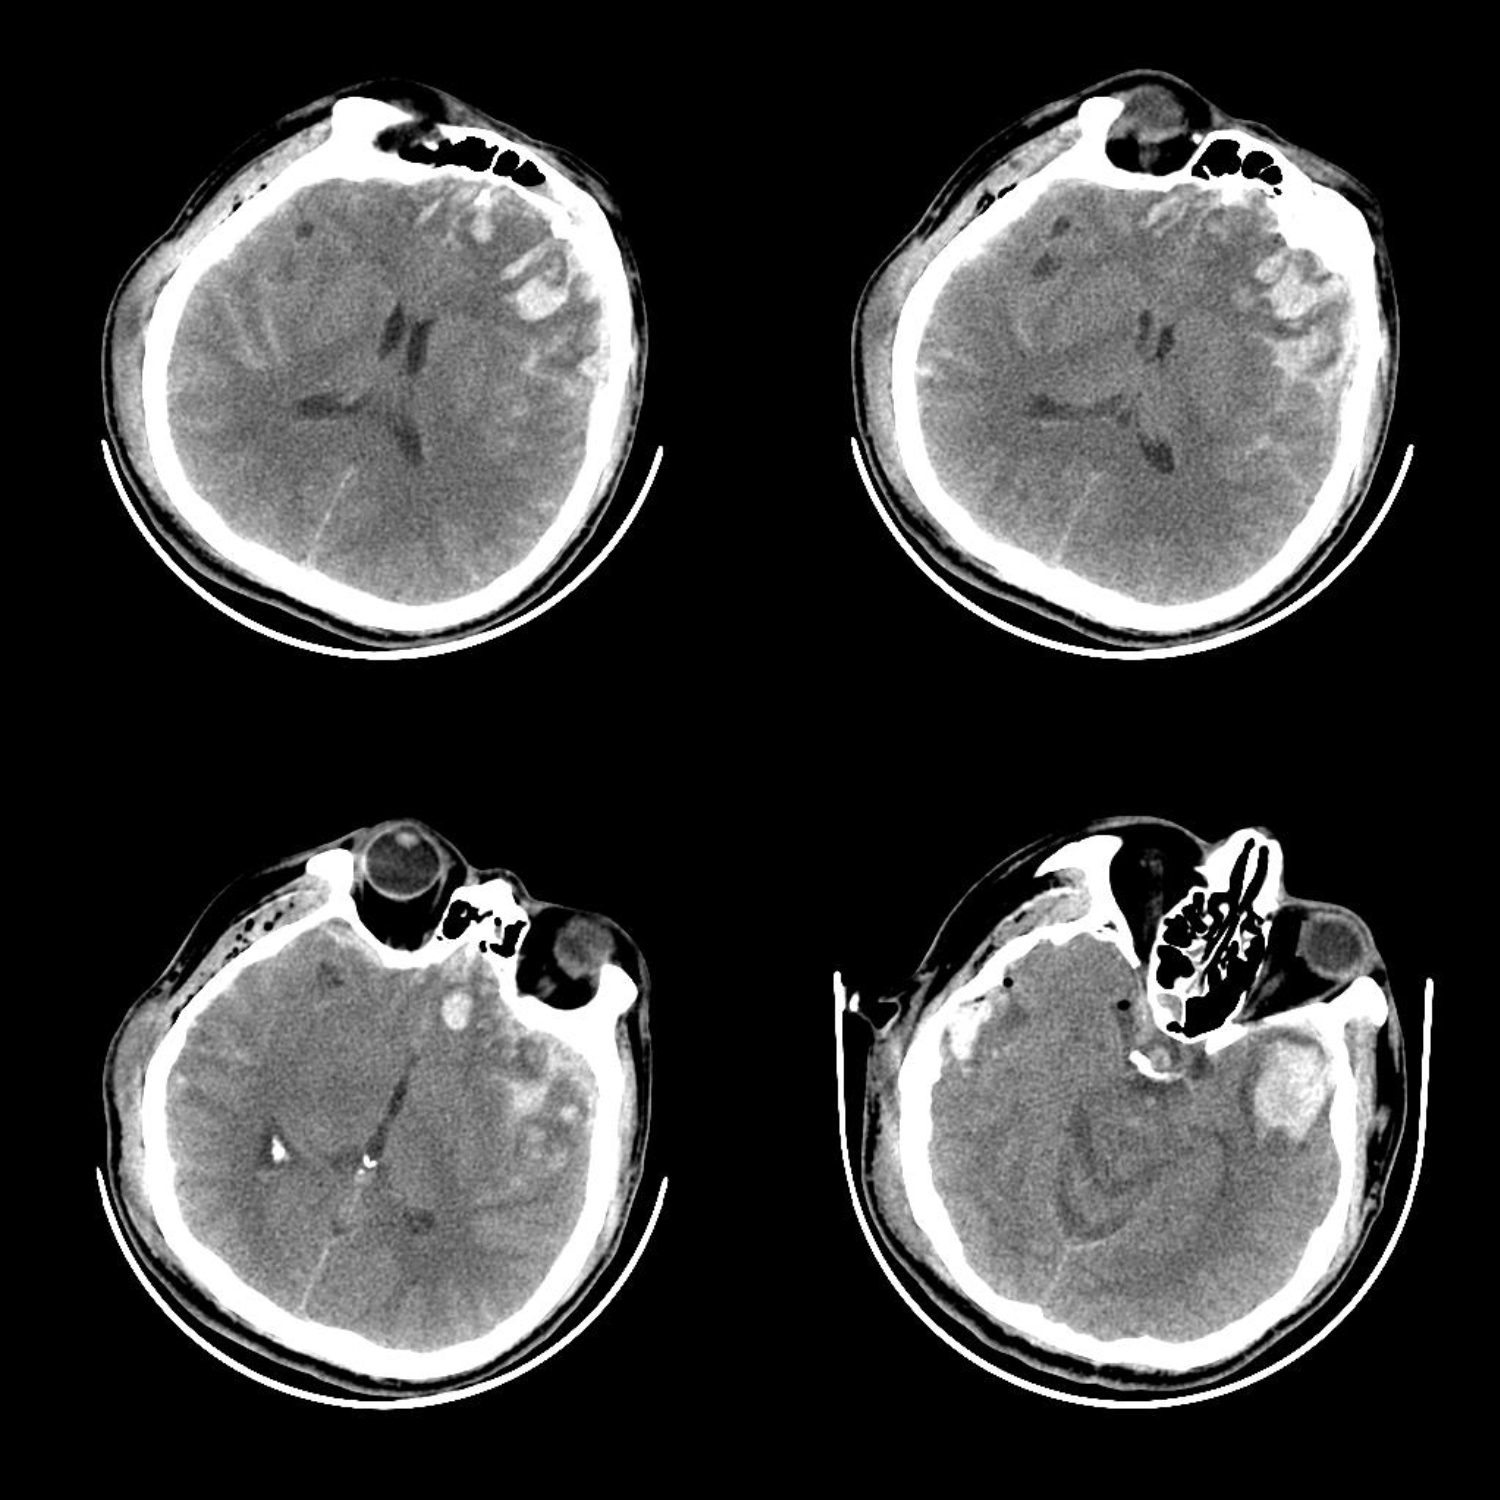

患者是一名50岁中年男性,主因车祸外伤后意识不清入院,头CT提示双侧额颞部多发脑挫裂伤,左侧为著

术前CT